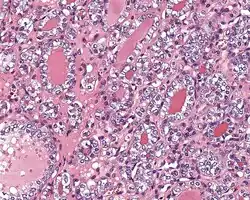

4) Must have the characteristic nuclear features of papillary thyroid carcinoma, although sometimes the features are patchy in distribution without all of the tumor showing those features. The nuclear features can be divided into three main categories:

- Nuclear size and shape: nuclear enlargement, nuclear elongation, and nuclear overlapping and crowding. Loss of nuclear polarity, with nuclei at the lumen, middle, or basal zone of the cells is also a helpful finding.

- Nuclear membrane irregularities: irregular nuclear contours, nuclear grooves and folds, "rat-bites" or demi-lune formations, and the presence of intranuclear cytoplasmic inclusions.

- Nuclear chromatin characteristics: nuclear chromatin clearing, often with condensation or margination along the nuclear membranes, resulting in accentuated nuclear margins, glassy nuclei, or fine, even delicate, powdery nuclear chromatin.

- ^ Image by Mikael Häggström, MD. Reference for findings: Rachel Jug, M.B.B.Ch., B.A.O., David Poller, M.D., Xiaoyin "Sara" Jiang, M.D. "NIFTP". Pathology Outlines.